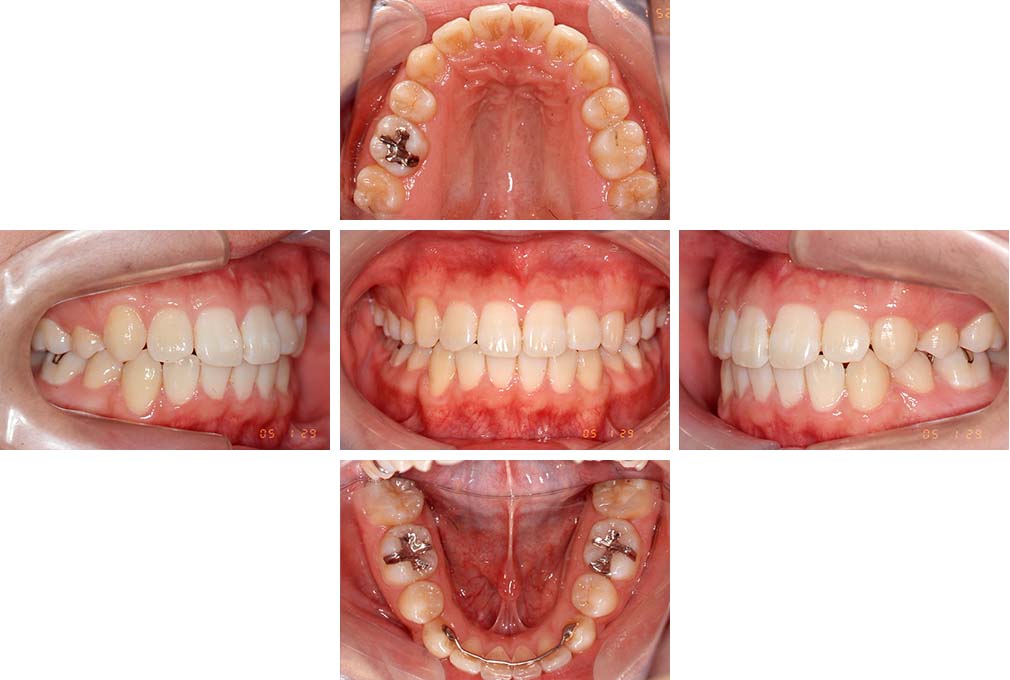

叢生を伴う骨格性上顎前突

初診時年齢 15歳10カ月

性別 男性

上顎前歯の前突と叢生を主訴として来院された。大臼歯関係は左右側ともにⅡ級で上顎の方が前方に位置していた。叢生を伴う骨格性上顎前突と診断し、上下顎小臼歯抜歯を行っていただきマルチブラケット装置に顎外固定装置を併用して動的治療を行った。顎外固定装置や矯正用ゴムの使用など協力状態も良好で、動的治療期間2年0カ月、調整来院20回でマルチブラケット装置を撤去し保定へ移行した。動的治療終了後10年0カ月を経過したが保定移行時とほぼ同様の咬合状態で良好な状態を保っていた。

治療前

15歳10か月

治療後

動的治療期間2年0カ月

18歳5か月

10年経過

動的治療終了後10年0カ月

28歳5か月